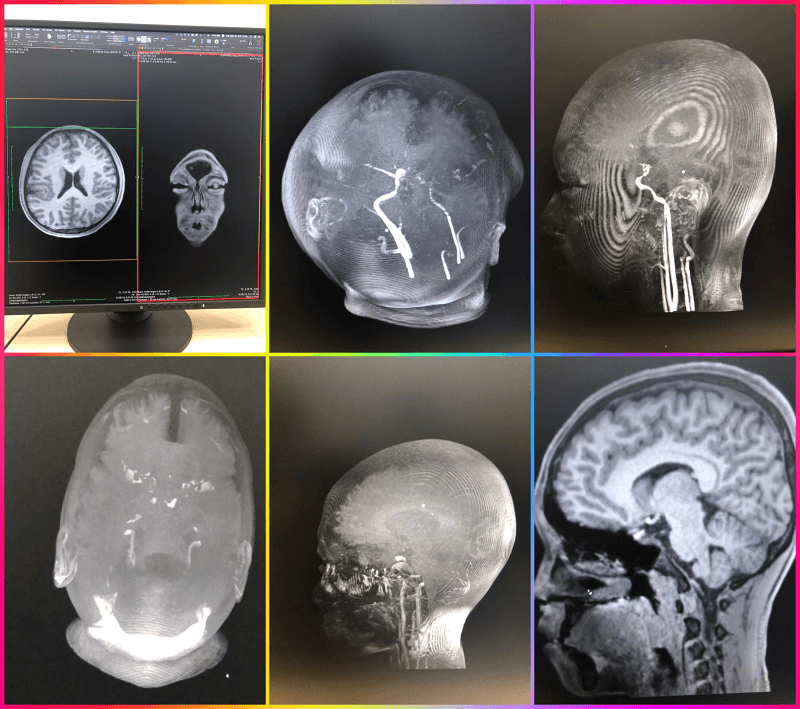

뇌과학 연구를 위해 한 대학교에 가서 찍은 아들의 뇌의 모습입니다. 실제로 두상이 예쁠 줄 알았는데 보는 것과는 많이 다르고 예쁜 두상을 가진 자녀들의 모습을 보는 순간 어렸을 적 관리를 잘해 줄 걸 하면서 후회가 막 밀려왔습니다.

사람의 뇌를 실제로 영상 품질이 높은 화면으로 보면 정말 신기하고 가느다랗고 투명한 실로 모두가 연결이 된 것을 보면서 신비로움은 이루 말할 수 없는데요 솔직하게 손발 눈 등도 신비롭지만 명령을 내리는 역할을 하므로 보이는 사진보다 더 투명하고 아름답게 보였습니다.

뉴로 게이 져 이흥렬 대표 : 뇌는 30살까지 최고 성장을 하고 그 이후부터는 성장을 멈추고 퇴화에 들어갑니다. 헉~~~ 깜짝 놀랐어요 제 나이가 그때 40대였으니 슬프기도 했습니다. 뇌를 위에서 상하로 움직이면 오른쪽에서는 위에서 바라보는 모습이 바뀌는 것을 보면서 신기하기도 했다

위 사진은 한 대학교 연구를 위해 참여 신청을 하고 촬영을 위해 어떤 약물을 먹고 3시간여 동안 촬영을 하면서 어떤 강점이 사람별로 있는지를 모듈화 하기 위해서 촬영한 부분인데 일정의 DNA가 어떤 강점을 가지고 있는지 다른 각도에서 사람마다 투명한 하얀색의 라인들이 모두 다르고 크기가 다른 것들을 비교해서 같이 참여했던 친구들과 볼 수가 있었는데 나중에 어른이 되어서 추적관리도 가능하다고 했고 자녀들까지도 어떤 구조로 성장을 하고 있는지를 추후에 파악을 한다고 이야기를 들었다

유명하신 뇌연구 이대열 교수님 동생인 뉴로 게이저 이흥열 대표가 정상인의 뇌의 정보를 구축하는 연구에 아들 참여 신청해서 검사를 했었는데 벌써 몇 년 전인데 지금까지 그 데이터를 모으고 벵크화 하는데 시간을 보낸 것 같아 연구의 길은 너무 힘들어 보입니다.